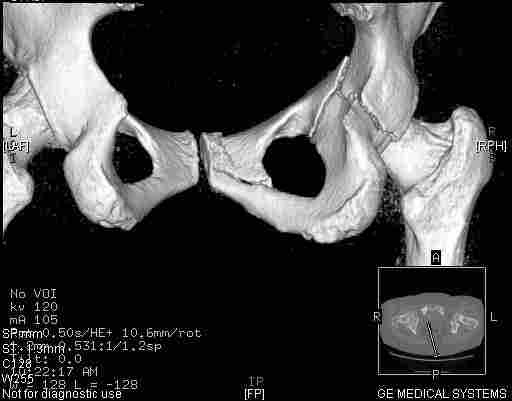

Следом 3d

|

Приветствую,Антон.Рункова рядом нет,но после полученных данных КТ,обсуждали совместно.Итог обсуждения-развернутый ответ дать не получится,т.к.срезы выбраны не информативные.Если ориентироваться на данные 3D,то ,ИМХО,можно лечить на вытяжении.